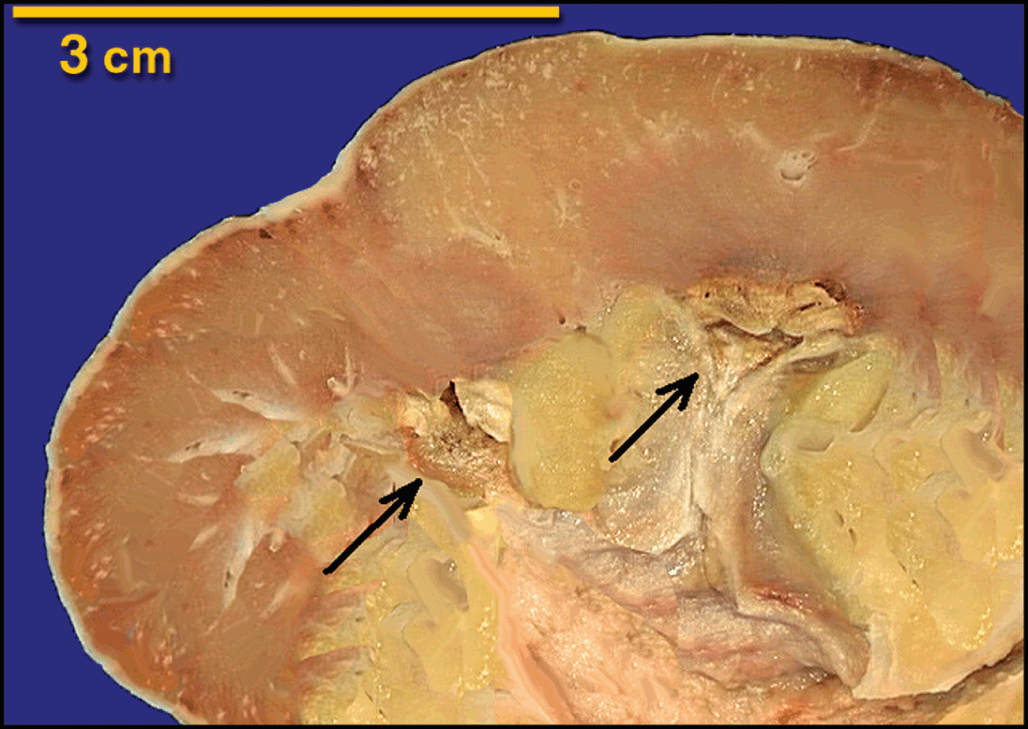

9b70fea5-1079-4abc-a0df-, Heptinstall's Pathology of the Kidney: 9781451144116,

Heptinstall's Pathology of the Kidney: 9781451144116, Heptinstall's Pathology of the Kidney: 9781451144116,

Heptinstall's Pathology of the Kidney: 9781451144116, Heptinstall's Pathology of the Kidney: 9781451144116,

Heptinstall's Pathology of the Kidney: 9781451144116, Renal Pathology of Ciliopathies - Thivya Sekar, Neil J,

Renal Pathology of Ciliopathies - Thivya Sekar, Neil J, Heptinstall's Pathology of the Kidney: 9781975161538,

Heptinstall's Pathology of the Kidney: 9781975161538, Non-neoplastic renal diseases (Chapter 31) - Silverberg's,

Renal Pathology of Ciliopathies - Thivya Sekar, Neil J, Practical Approach to Congenital Anomalies of the Kidneys,

Practical Approach to Congenital Anomalies of the Kidneys, Cystic Diseases and Developmental Kidney Defects | Abdominal Key,

Cystic Diseases and Developmental Kidney Defects | Abdominal Key, The Aging Kidney and End-stage Renal Disease (Chapter 15,

Tubulointerstitial Diseases (Chapter 12) - Silva's, Diagnostic Pathology: Kidney Diseases: 9780443107177

Diagnostic Pathology: Kidney Diseases: 9780443107177